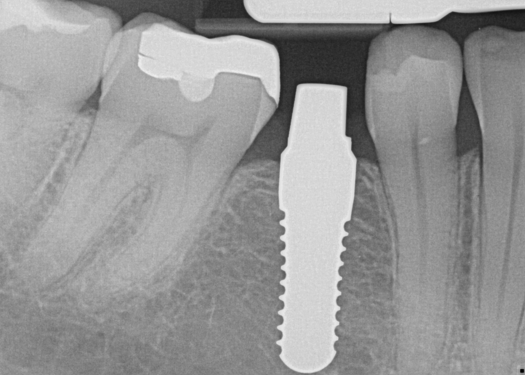

Fig 17. 12-week postoperative radiograph.

Figure 17

The final impression appointment follows the light-load phase, provided the implant is stable and the soft tissue is acceptable to the clinician. Polyvinyl putty and light-body impression materials were used in this case; analog casts and final full-zirconia full crowns were fabricated (Figure 16). The patient provided feedback that chewing was comfortable and without food impactions. Keratinized gingival cuff was developed, and natural-tooth contours for the restorations mimicked what is normally found in human dentition. The healed bone surrounding the ceramic dental implant was similar in density and crestal levels in comparison with the adjacent natural teeth, evident in the radiographic evaluation (Figure 17). Final long-term restorations at the gingival crest and restoration interfaces were also consistent in optimum periodontal health and gingival height. Arch-form integrity was upheld and occlusion was managed; osseointegration and light-load principles optimized the success of the restorations, and an acceptable, harmonious esthetic outcome was achieved for the patient.